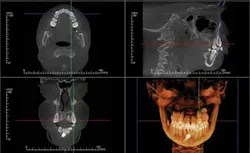

All CBCT manufacturers include OEM (Original Equipment Manufacturer) software with their machines. This software varies with the specific units, but generally includes a method of viewing the scan in an interactive frontal, sagittal, and coronal mode known as Multi-Planer Reconstruction (MPR). Each scan is reviewed first by browsing through the cross sections in all three planes and noting any findings, with particular attention paid to the diagnostic condition of interest (Figure 1).

Specialized orthogonal cross sections, such as panoramic planings, are performed to elicit a more directed view of areas of interest. The Hounsfield density measures the relative density of the involved structures and offers insight into the nature of the lesion. Most OEM software includes a 3-D viewer which can be applied to the scan to observe the volume of the target and its juxtaposition to other structures. Measuring tools in the software enable precise measurements in both the 2-D and 3-D images. The 3-D images can be cropped to decrease superimposition of adjacent structures — surface rendered to view skin and airway volume — all of which can be rotated for viewing at any angles. Most OEM packages have a function which displays corrected tomographic AP and coronal slices through the temporomandibular joints.